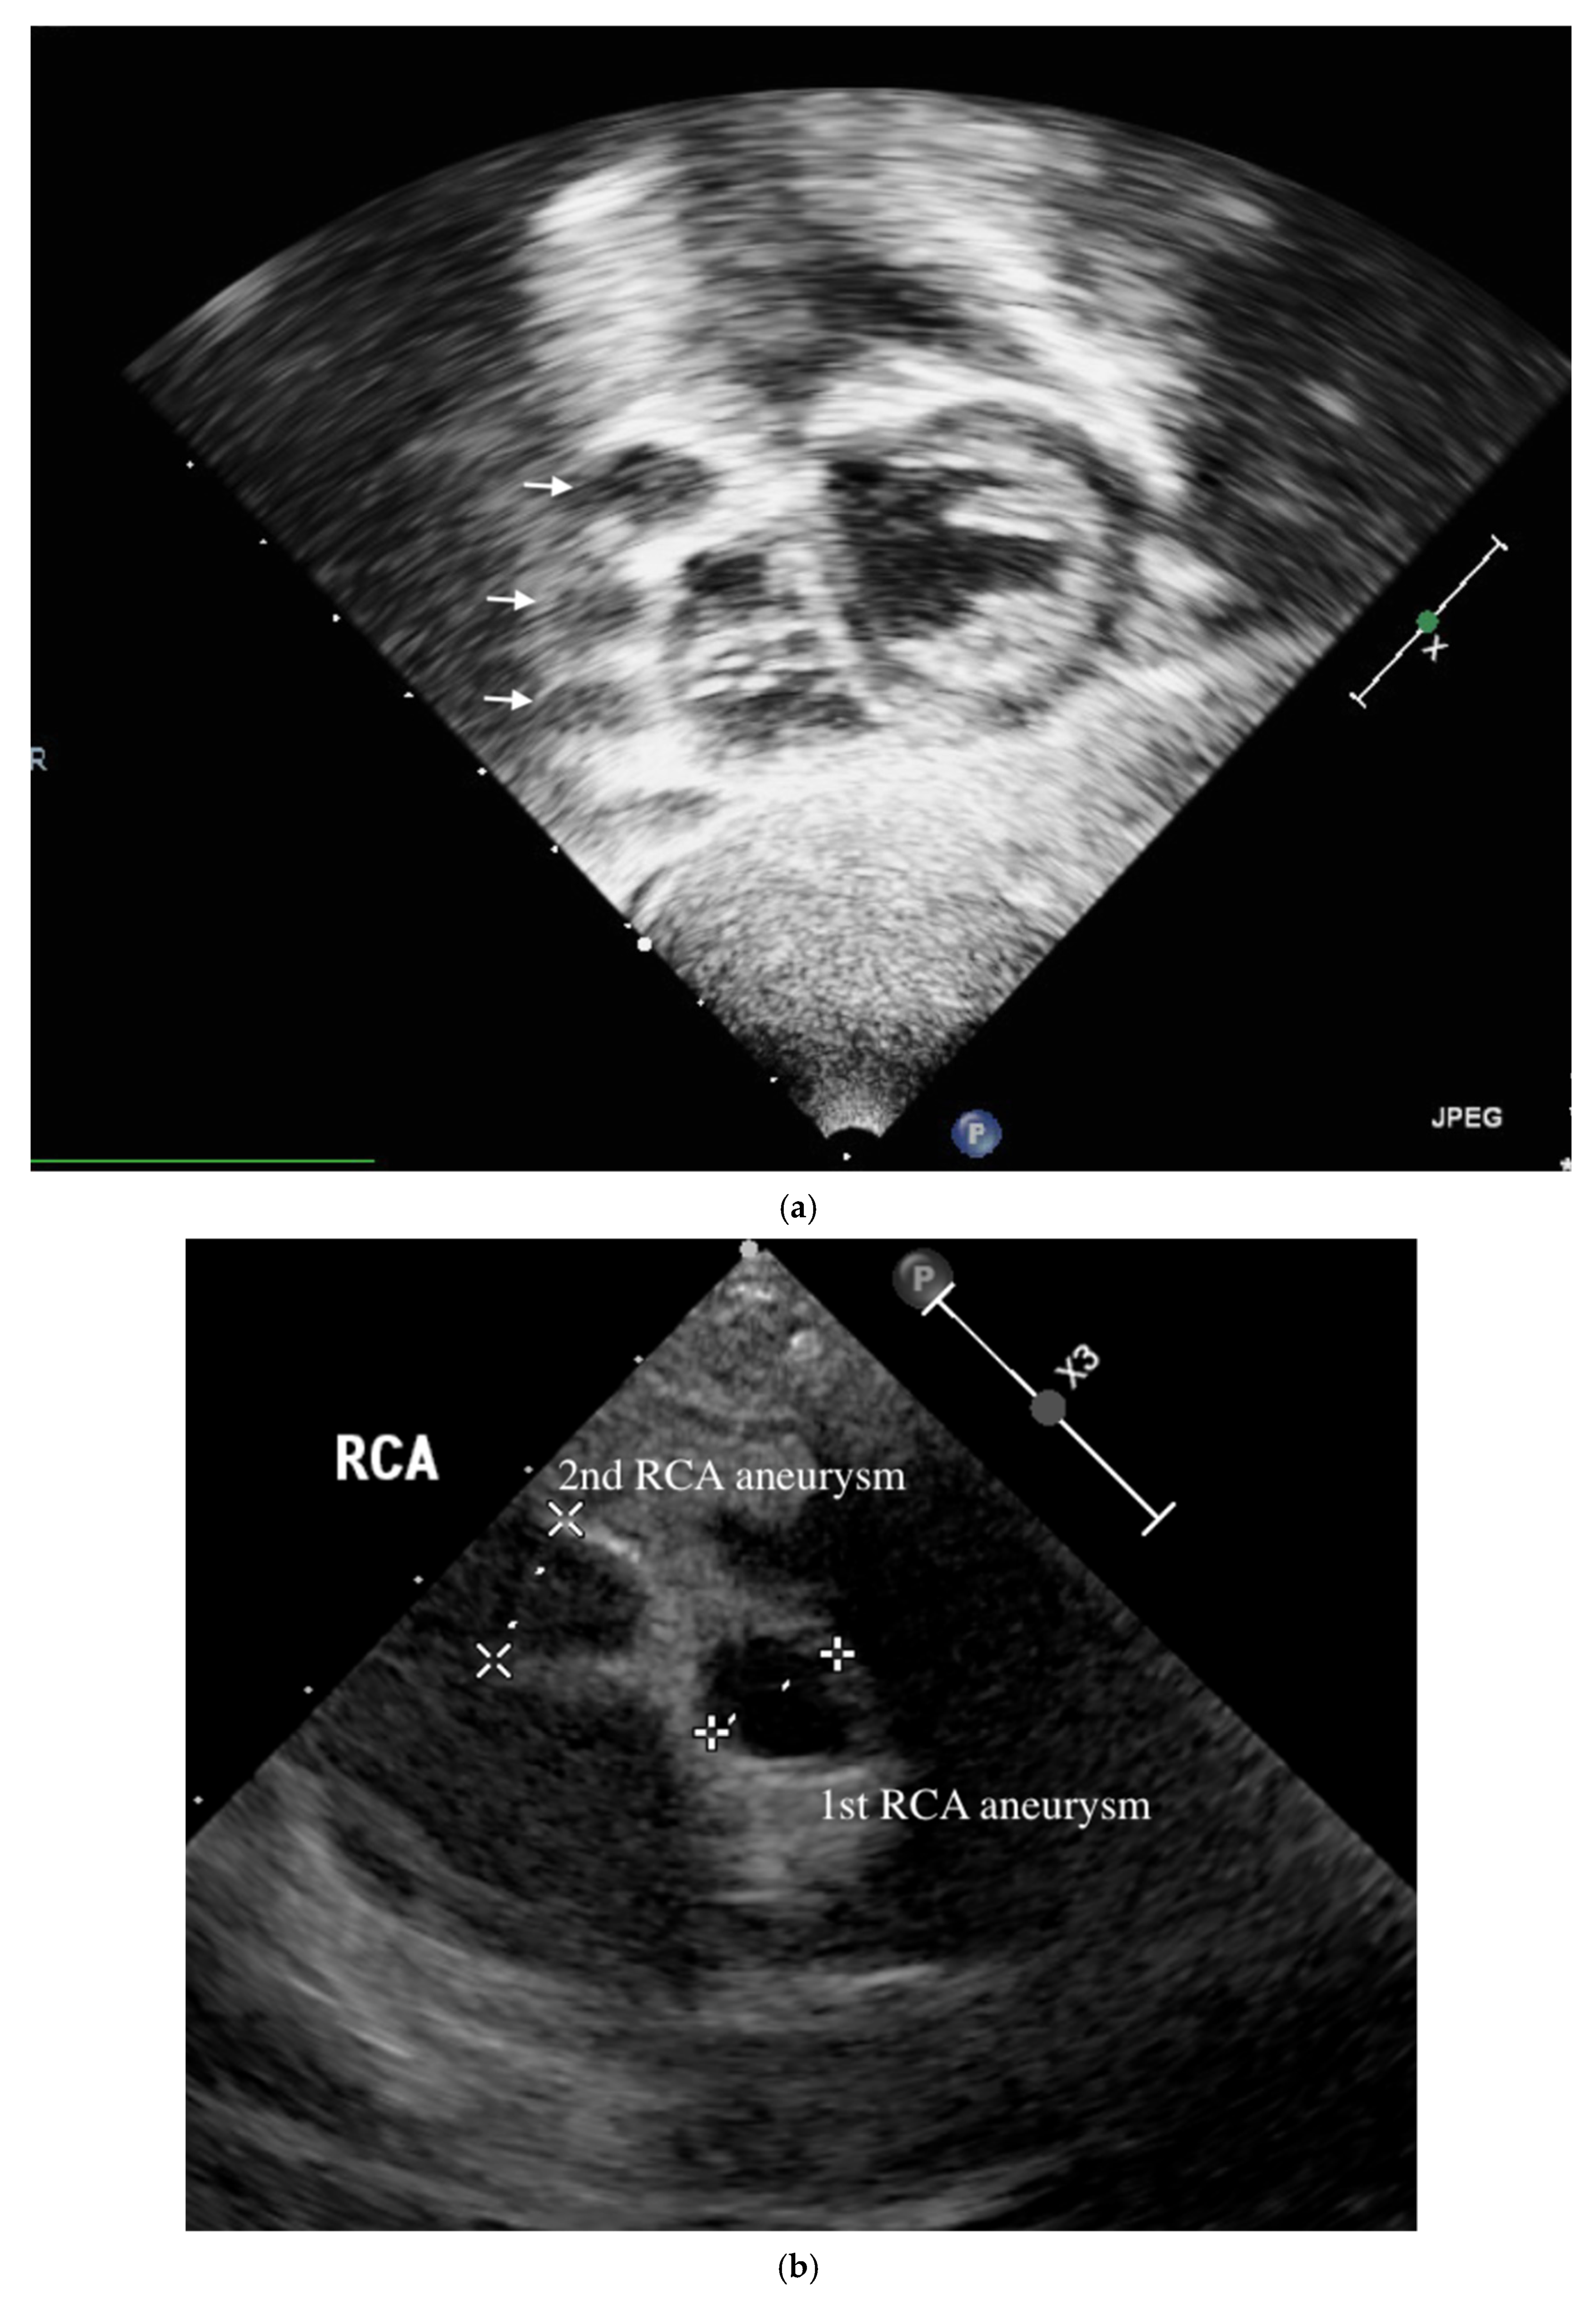

A 4-month-old infant girlwho presented with intermittent fever without explanation for 14 days was admitted.Laboratorydata revealed leukocytosis (19.5 × 109/L), high sensitivityC-reactive protein (CRP, 1139.04 nmol/L), and thrombocytosis (590 × 109/L). Negative culture reports were found in blood and urine. The empirical antibiotics administration did not achieve clinical improvement. The subcostal view of echocardiography andtransthoracic echocardiography (TTE) revealed three giant fusiform aneurysms of the proximal right coronary artery, along with other smaller aneurysms in the left coronary system. (Figure 1) Acute mitral insufficiency with moderate pericardial effusion was also present. The three beaded aneurysms were subsequently confirmed on a selective right coronary angiogram. (Figure 2) The fever resolved after receivinga high-dose intravenous immunoglobulin (IVIG) infusion. Aspirin with anticoagulant drugs (subcutaneous injection of low molecular weight heparin) administration was initiated and serial echocardiography as well as invasive coronary angiography follow-up were regularly performed sincethe giant aneurysm’s detection. (Figure 3) This report revealeda “beaded aneurysm” as a special medical image for KD.Itsfundamental nature of non-contiguous aneurysms could be a key to identifying antecedent KD vasculopathy compared toother coronary artery aneurysms. Written informed consent was obtained from the participant for the publication of this case report.

A pediatrician must check the echocardiography imaging of coronary arteries in infants with prolonged fever and evidence of elevated inflammation markers whenever the reasonable cause is absent because positive echocardiography findings were regarded as a set standard for acute KD accordingly. Coronary aneurysms can occur in up to 25% of KD children without a timely infusion of high-dose IVIG such as in this index case.As coronary aneurysms have become rare due to the widespread use of IVIG therapy for KD, beaded aneurysm is considered to be even rarer. There are no reports on the frequency of beaded aneurysms in KD, but it is presumed to be relatively rare.The final size of coronary aneurysms defines the future risk stratification generally speaking. In small or medium-sized aneurysms (<8mm or Z score <10), spontaneous regression of the aneurysms without significant cardiovascular sequela such as long-term luminal myofibroblastic proliferation is possible. In this case, the subcostal view of echocardiography and TTE revealed three giant fusiform aneurysms of the proximal right coronary artery, along with other smaller aneurysms in the left coronary system (Figure 1a–c). The three beaded aneurysms were confirmed by coronary angiogram is showed in Figure 2. In contrast with smaller aneurysms, giant aneurysms (>8 mm or Z score >10) seldom or never regress over time, which could be observed from the timeline of the index case(Figure 3).

Figure 1. Transthoracic echocardiology on the 16th months after illness of aneurysm. Three RCA aneurysms in a beaded arrangement from the subcostal view of echocardiography (a) and transthoracic echocardiogram imaging showed first with second RCA aneurysm (b) as well as first with third RCA aneurysm (c).